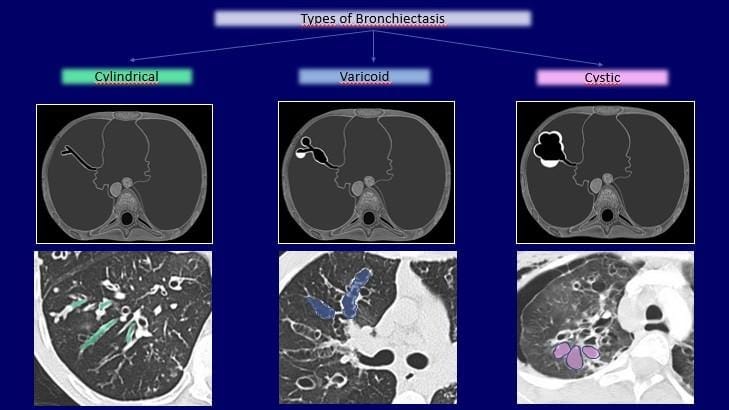

• Chest CT scan or a chest X-ray